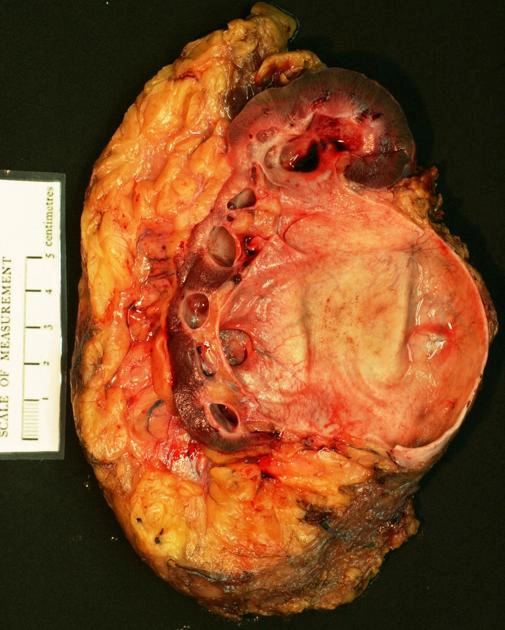

Thận móng ngựa (Horseshoe kidney)